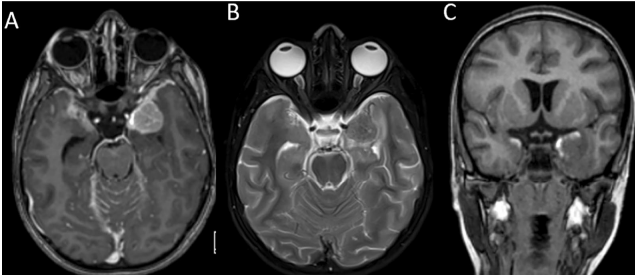

Abstract Primary diffuse meningeal melanomatosis (PDLM) represents a rare and aggressive form of primary central nervous system (CNS) melanoma, with only 32 cases reported in the literature [1]. Given its...